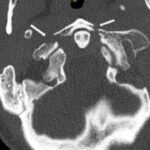

The Jefferson fracture classification system describes fractures of the atlas (first cervical vertebra or C1). Jefferson fractures with potential tears in the transverse ligament can cause cervical spine instability and can result in neurologic injury if not appropriately diagnosed and managed. We present the case of a 54-year-old man who fell head first with cervical spine tenderness and upper extremity paresthesias. The patient’s Jefferson fracture was diagnosed via computed tomography. The patient was then treated non-operatively for his Jefferson fracture, and he had an unremarkable hospitalization. Emergency physicians should obtain surgical consultation and consider the possibility of ligamentous injury in patients suffering injury to the cervical spine.